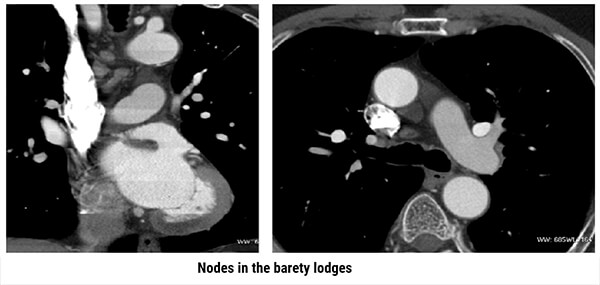

Multi Planar Reconstructions

Both images show the presence of nodes in the Barety lodge, or Baréty’s box (or right pre-tracheal space). It is an anatomical space located in the middle mediastinum of the human thorax which is formed of a cellulo-lymphatic tissue running along the trachea.